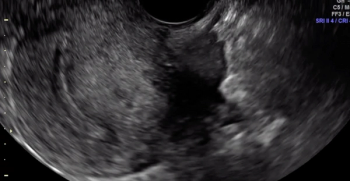

Pressure is being applied to the uterus by the ultrasound operator’s non-scanning hand, eliciting smooth sliding of the posterior uterine serosa over the bowel. Some fluid is noted within the rectouterine pouch, which often suggests a non-obliterated pouch

A hypoechoic deep endometriosis nodule is noted within the hyperechoic uterosacral ligament, infiltrating the parametrium